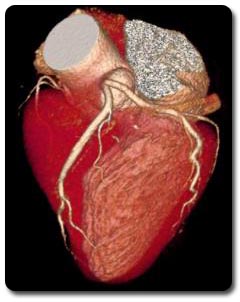

Evaluación de coronarias 3D

Por primera vez en Guadalajara le presentamos las nuevas secuencias 3D para estudio de las arterias coronarias por cardio-RM, las cuales permiten obtener imágenes resolutivas de sus segmentos proximal y medio, sin la necesidad de utilizar contraste paramagnético, de utilidad para la práctica clínica.

Las principales ventajas de nuestro nuevo cardio-RM son la ausencia de radiación ionizante así como de contrastes yodados. La posibilidad de estudiar las arterias coronarias en el momento actual, culmina el concepto de “todo en uno” ( one stop shop) como la técnica que puede valorar en un solo estudio todo el espectro anatómico y funcional de la cardiopatía isquémica.

“La forma mas eficiente de observar la correlación anatómica y funcional”.